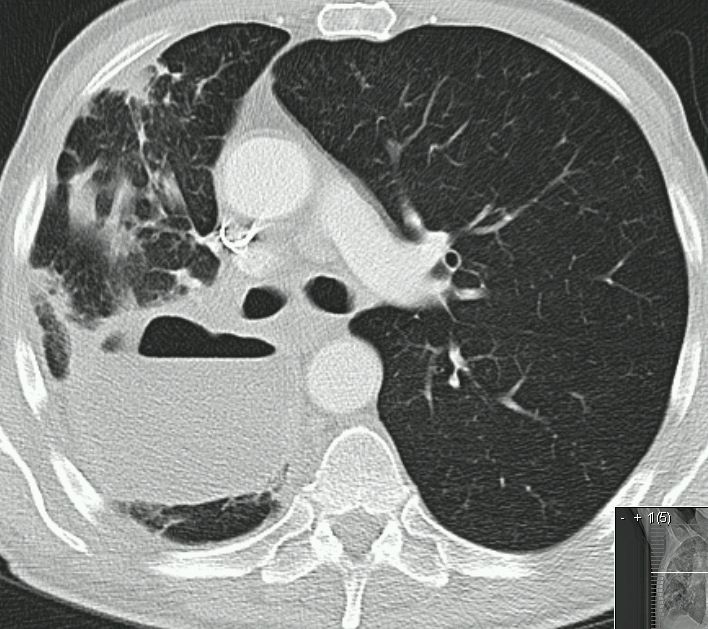

| Thoraxwanddestruktion | Plattenepithelkarzinom des rechten

Lungenoberlappens mit Destruktion der Thoraxwand und mediastinalen

Lymphknotenmetastasen. ![]() |